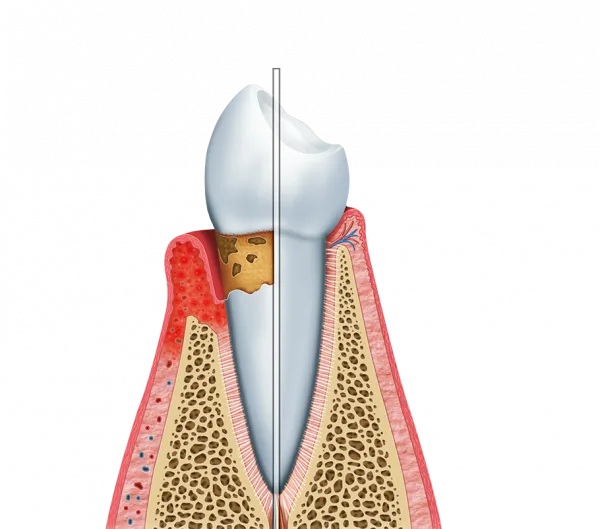

O tratamento gengival moderno é uma abordagem inovadora na Periodontia, focada na saúde das gengivas e dos tecidos de suporte dos dentes.

Este tipo de tratamento é essencial para prevenir e tratar doenças periodontais, que podem levar à perda dentária se não forem adequadamente geridas.

O tratamento gengival moderno envolve técnicas que visam a saúde e a estética das gengivas.

Ele é vital para manter a integridade da boca e prevenir complicações futuras.

As técnicas de tratamento gengival evoluíram significativamente nos últimos anos.

Antigamente, os métodos eram mais invasivos e dolorosos.

Hoje, com o uso de tecnologias como laser e ultrassom, os procedimentos são menos traumáticos e mais eficazes.

Os métodos tradicionais de tratamento gengival muitas vezes envolviam cirurgias extensivas.

Em contraste, o tratamento gengival moderno utiliza abordagens minimamente invasivas.

Prevenção de doenças periodontais

O tratamento gengival moderno é crucial para a prevenção de doenças periodontais.

Ele atua no controle da placa bacteriana e na redução do tártaro.

Isso ajuda a evitar problemas mais sérios, como gengivite e periodontite.